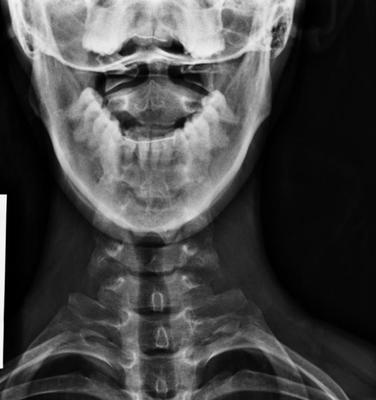

Firstly your cervical spine has a sharp kyphosis; clearly you've had a nasty whiplash with tearing of ligaments, and probable injury to the desk.